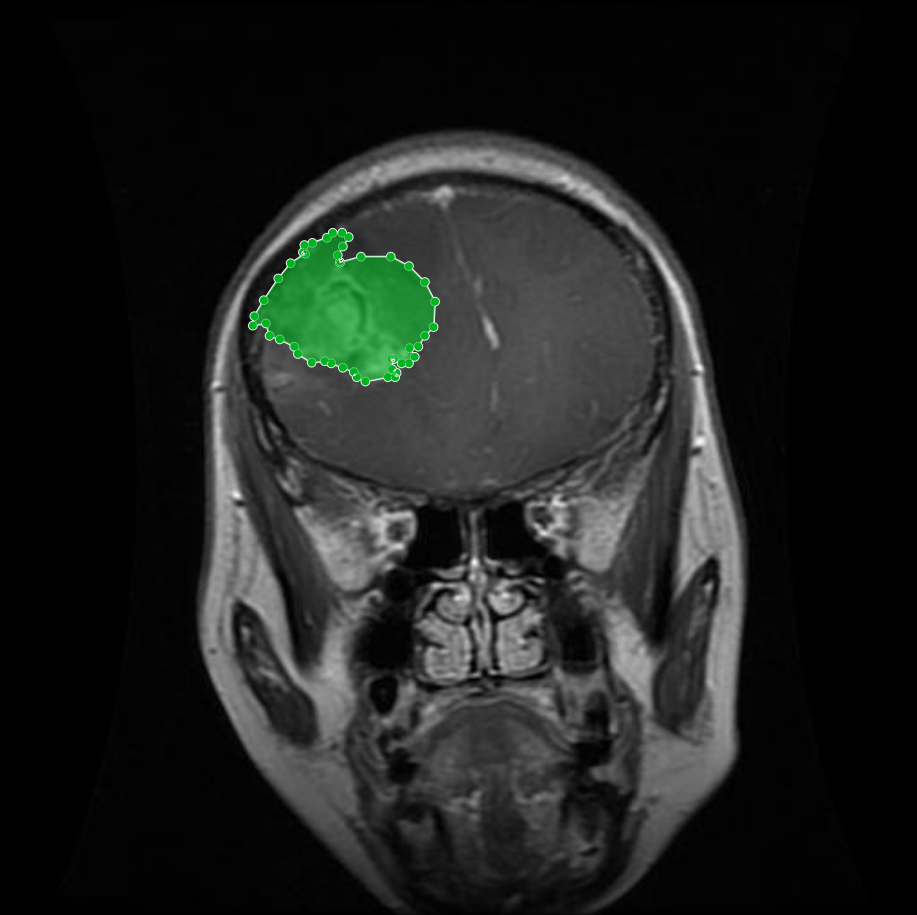

Figure 3: Samples of Pituitary segmentation across different imaging planes

Pituitary Tumors: Located at the base of the brain near critical structures like the optic chiasm, pituitary tumors demand careful delineation to avoid diagnostic errors. As shown in Figure 3, the segmentation accurately captures the tumor’s boundaries without encroaching on adjacent critical regions.